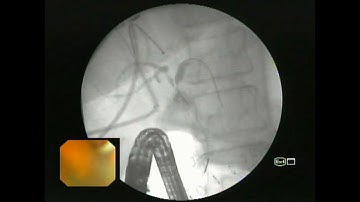

ERCP ; Large proximal CBD stone impaction with suppurative cholangitis for stentng.